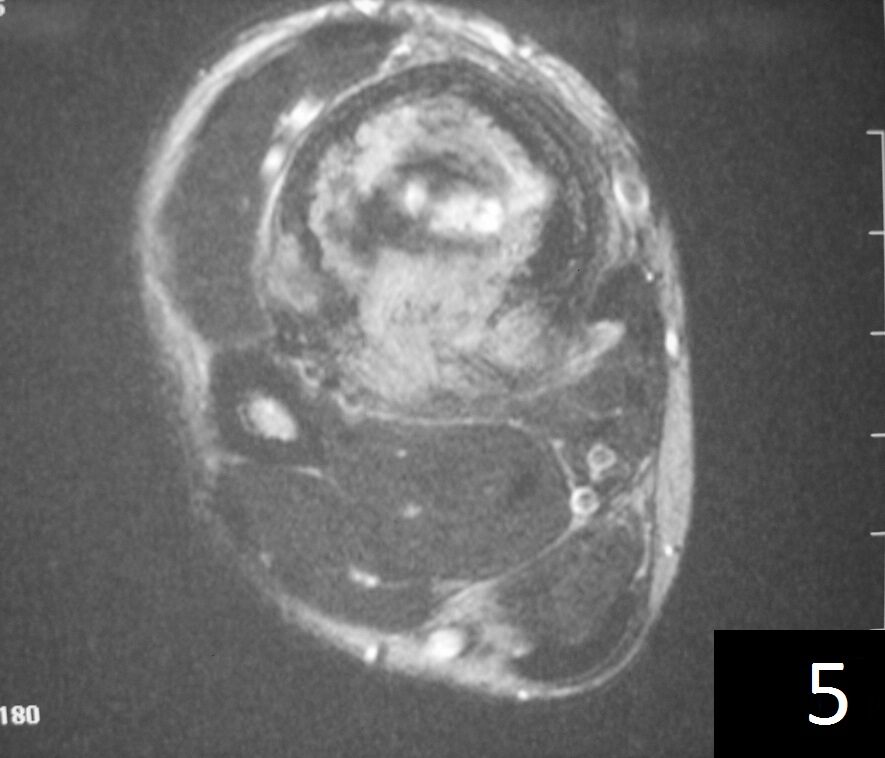

MRI (Fig. 4-5)

Fig. 4

Fig. 5

Fig. 4-5: Axial MRI of leg demonstrates a tibia lesion with cortical destruction and soft tissue involvement.